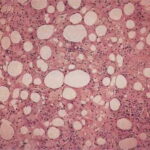

Histopathology. The histopathologic appearance itself is not sufficiently specific to exclude other diseases . The classical description of the disease is that it evolves through three stages. In the first phase, there is only erythema and induration clinically. Histologically, acute inflammation is found in the fat lobules with degeneration of fat cells and an infiltrate of neutrophils, lymphocytes, and macrophages. The second phase has an infiltrate discretely localized to the fat lobules, consisting mainly of macrophages, foam cells, and extracellular lipid droplets. In some cases, the lesions perforate the skin surface and discharge a sterile, oily liquid. The third phase |

has depressed and indurated clinical lesions. Fibroblasts, collagen, and scattered lymphocytes and a few plasma cells replace the fat. Vascular changes are mild . |